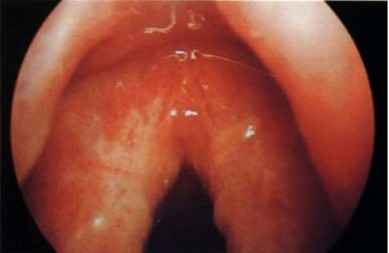

1、颈项咽喉周围有甲状腺和甲状旁腺、颌下腺、腮腺等内分泌器官,当颈项咽喉部炎症或其它病变时,容易通过淋巴管的分支扩散到这些内分泌器官,引起相应的内分泌器官病变,使内分泌失调,出现相应疾病。例如上呼吸道感染可并发腮腺炎、甲状腺炎等。

2、咽喉部的炎症可以启动全身的免疫系统,对侵入的细菌病毒进行攻击,对正常组织进行保护。但是因为咽喉部刺激因素的强弱久暂不一,这些免疫反应有时不足,有时过强。不足就是免疫力低下、过强就是免疫力增强,不管是不足还是过强都会出现全身性疾病。例如肾小球肾炎就是对于咽部链球菌免疫力增强的结果。 >>>推荐阅读:咽生殖器畸形原因症状大比拼

3、头颅与躯体是依靠颈项的颈椎、肌肉来连接支撑的,头颅的转动是最频繁、最灵活的复杂关节,咽后壁的炎症可以导致颈椎椎体不稳,出现颈椎病。而颈椎病可能是引起高血压、低血压及血压波动的重要原因。咽喉壁的炎症可以蔓延到颈椎部位的软组织,使颈部交感神经节受到刺激,使支配心脏、椎动脉的神经功能失调,出现心慌、头晕、失眠等等症状。

4、咽喉部肿胀会影响食物的吞咽。咽喉部的炎症或其它病变刺激食管支配神经,引起膈肌痉挛,会出现呃逆、心下痞等症状。